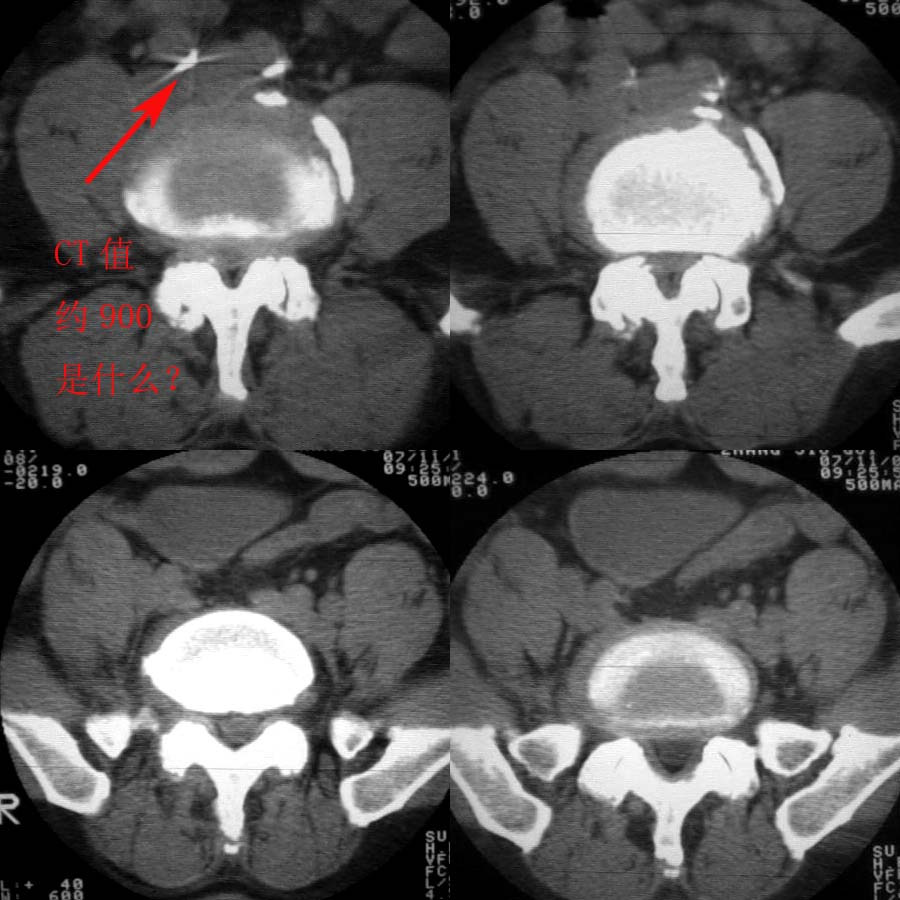

男57岁,腰痛,双腿麻木,请各位老师帮忙看看箭头所指是什么?ct值约900-1000hu是钙化影吗?

双侧髂总动脉钙化.

如此高的ct值除了钙化还有什么?当然本病例不是金属异物了。

均为钙化,可形容为金属感.

是右侧髂总动脉壁粥样硬化斑钙化,左侧亦有。

退行性骨关节病。